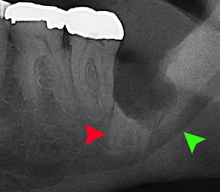

Coronectomy is a procedure used when the surgeon believes that there is a high risk of inferior alveolar nerve injury. After making the incision in the mucosa and removing bone adjacent the tooth, the crown is cut and removed with no attempt at removing the roots. It is indicated when there is no disease of the dental pulp or infection around the crown of the tooth and there is a high risk of inferior alveolar nerve injury.

Coronectomy, while lessening the immediate risk to the inferior alveolar nerve function has its own complication rates and can result in repeated surgeries. Between 2.3% and 38.3% of roots loosen during the procedure and need to be removed and up to 4.9% of cases require reoperation due to persistent pain, root exposure or persistent infection. The roots have also been reported to migrate in 13.2% to 85.9% of cases.[27]